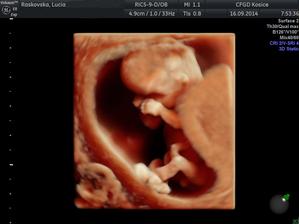

♥ 16.september prvotrimestrálny skriníng v 12tt (v Myslave) všetko v poriadku, odber krvi a máme prvé 3D fotky a na 80% potvrdené pohlavie 🙂